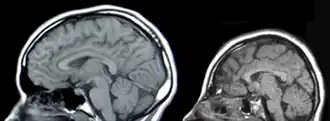

- F7x.x8 — …обусловленная другими уточнёнными причинами (например: врождённая аномалия головного мозга, краниосиностоз, микроцефалия, гипертелоризм и т. д.)